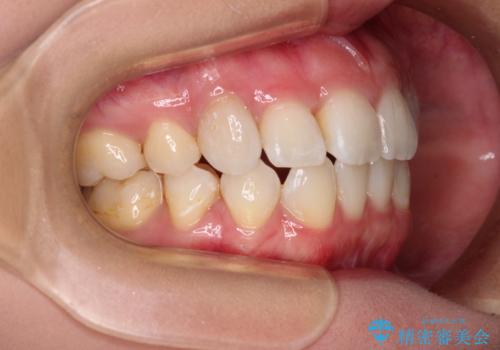

上顎の八重歯と下顎前歯の欠損 ワイヤー装置による抜歯矯正

- 上顎の八重歯を気にして来院された患者様です。

診察したところ、下顎前歯が2本欠損していたため、上下のバランスを取りながら八重歯を改善するため、上顎左右第一小臼歯2本を抜歯することとしました。

下顎左右大臼歯の歯根部に病変があったため、矯正治療前に根管治療を行い、矯正治療後にセラミッククラウンによる補綴治療を行うこととしました。

下顎前歯と本来抜歯矯正で抜歯する歯とは大きさが異なるため、仕上がりの咬み合わせは理想的なものとはなりませんでしたが、気になっていた八重歯はきれいに改善することができました。